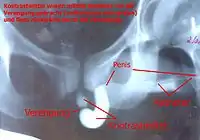

Radiografía de una retrografía retrógrada

El procedimiento implica la inserción de una sonda de Foley en la «fosa navicular» que es el punto más amplio de la apertura de la uretra a nivel del glande masculino. A ese nivel se infla levemente el balón de la sonda con 1 a 2 ml de líquido. Ello es seguido por la lenta inyección de 30mL de contraste soluble en agua mientras se obtienen varias radiografías sencillas con la persona en posición oblicua al plano de la radiografía para poder observar la uretra en la imagen.[2] El escape del contraste fuera de la uretra sugiere daño uretral (normalmente secundario a trauma pélvico) y es indicación para una intervención quirúrgica reparadora.[3]